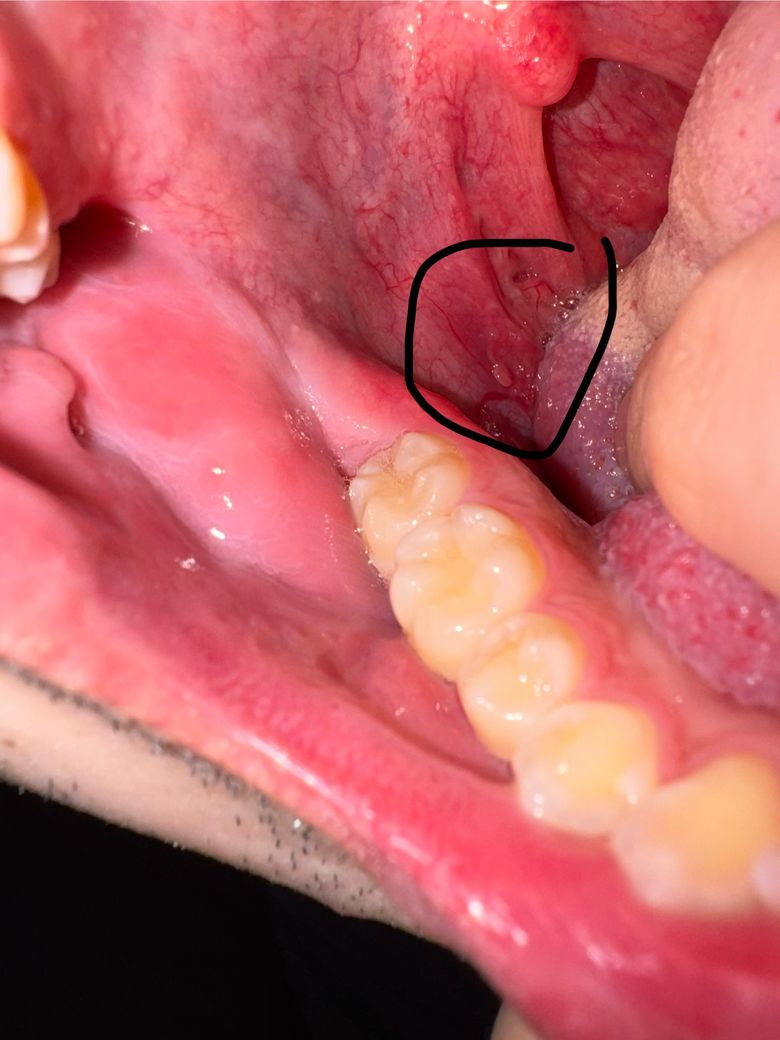

• 3번 째 사진

• 사진상 위치는 혀 옆면 하부, 구강저 부위로 보이며, 점막이 약간 돌출되고 주변 혈관이 확장되어 보입니다. 통증이나 이물감이 없는 점을 고려하면 급성 염증성 병변보다는 양성 변화 가능성이 높습니다.

가장 흔한 원인은 다음과 같습니다. 첫째, 점액낭종으로 침샘관이 막히거나 손상되면서 점액이 고여 작은 혹처럼 보일 수 있습니다. 무통성이고 투명하거나 붉게 보일 수 있습니다. 둘째, 국소 혈관 확장 또는 경미한 점막하 출혈입니다. 혀를 씹거나 자극이 반복되면 혈관이 도드라져 보이거나 멍처럼 보일 수 있습니다. 셋째, 섬유성 증식으로 반복 자극에 의해 살짝 솟은 조직이 생기는 경우입니다.

현재 소견만으로는 악성 가능성은 낮아 보입니다. 일반적으로 구강암은 지속적인 통증, 단단한 결절, 궤양, 쉽게 출혈, 2주 이상 지속되는 비치유성 병변 형태로 나타나는 경우가 많습니다. 사진에서는 그런 특징은 뚜렷하지 않습니다.